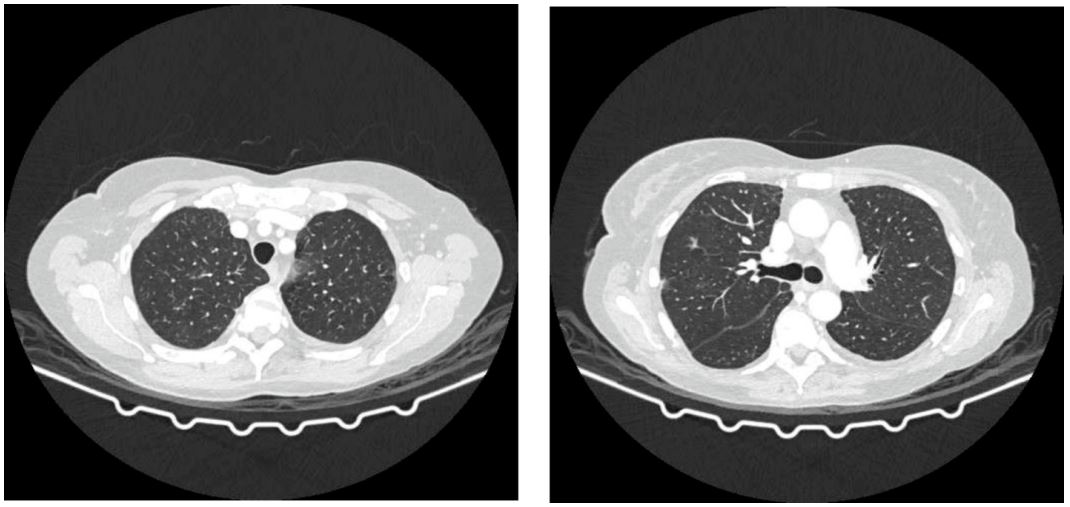

Figure 1: Chest scanner with GGO-type zones as part of ILD/pneumonitis.

On the X-ray of the heart and lungs, bilateral pleural effusions were present, more pronounced on the right. An urgent CT scan with contrast pulmonary angiography was performed, showing no signs of pulmonary thromboembolism (Figure 1).

A CT scan with contrast was performed, showing bilaterally present pleural effusions, more pronounced on the right. Diffuse in the visible part of the lung parenchyma, interlobular septa with GGO-type zones are highlighted on both sides in the upper lobes and the lower left lobe (Figure1). The clinical findings were worse than the radiographic. GGO- ground-glass opacity.

In the MONARCH 3 trial, which compared the combination of abemaciclib and an aromatase inhibitor to an aromatase inhibitor alone in untreated postmenopausal women with HR-positive, HER2-negative locoregionally recurrent or metastatic breast cancer, one patient treated with the combination died from pneumonitis. In the MONARCH 2 trial, which compared the CDK4/6 inhibitor + fulvestrant to fulvestrant alone in women with HR-positive, HER2-negative advanced or metastatic breast cancer who have disease progression following endocrine therapy, two patients died from pneumonitis. The MONARCH 2 trial’s results supported the approval of abemaciclib [11]. According to the prescribing information, cases of interstitial lung disease/pneumonitis were also reported after approval [12]. Ribociclib in combination with an aromatase inhibitor was also approved in 2017 as initial endocrine-based therapy for postmenopausal women with HR-positive, HER2-negative advanced or metastatic breast cancer [11]. There is less evidence showing the link between CDK-4/6 inhibitors and pulmonary toxicity. The articles on pablociclib- and abemaciclib-induced lung injury illustrate the potentially fatal drug-associated lung injury that may be associated with them. After four weeks of ribociclib use, our patient developed pneumonitis, which is uncommonly reported in the medical literature. The multi-slice chest scan revealed ILD/pneumonitis with GGO-type zones that were highlighted on both sides in the upper lobes and the lower left lobe, as well as bilateral pleural effusion (Figure 1). The clinical findings were worse than the radiographic (Figure 1). Therefore, ribociclib was discontinued along with starting methylprednisolone (1.5 mg/kg/day), with noticeable clinical improvement within 1 week. Six week later a control CT chest scan displayed progression of the previously described zones in the lung parenchyma according to the type of GGO (Figure 2). The patient was clinically better, but the control radiographic finding was in progression. Therefore, the pulmonologist prescribed corticosteroid therapy according to the following scheme: 40 mg of prednisone once daily for 3 weeks, then 30 mg of prednisone once daily for a month, then 20 mg of prednisone once daily for 3 months. After 3 months of therapy by a pulmonologist, the patient underwent a control scan of the chest and abdomen, which described a complete regression of zones according to the type of GGO as part of ILD/pneumonitis (Figure 3). In addition, previous real-world study based on the FAERS database showed that a median latency of 63 days (range 21-136) for CDK4/6 inhibitor-associated ILD [1]. This finding was in line with the results from an adverse event-time analysis of abemaciclib and palbociclib using data from Japanese Adverse Drug Event Report (JADER) database, suggesting that both abemaciclib and palbociclib were associated with the onset of ILD after 1-2 months from the start of treatment [29]. A retrospective study of drug-induced ILD demonstrated that, there was a certain similar trend in the timing of the occurrence of ILD induced by most anticancer drugs, most of which occurred within 3 months [30]. There are no known risk factors for the development of lung inflammation associated with CDK4/6 inhibitor use [11]. For patients with severe interstitial lung disease and/or pneumonitis who develope new or worsening pulmonary symptoms, the FDA recommends interrupting treatment and permanently discontinuing CDK4/6 inhibition and initiating corticosteroids [26]. It is essential for clinicians to remember that fatal interstitial pneumonitis can occur in ribociclib-treated patients (even after only four weeks into treatment), as early diagnosis can be crucial [9]. Besides early diagnosis of ILD/pneumonitis proper and continuos usage of corticosteroids is also crucial.